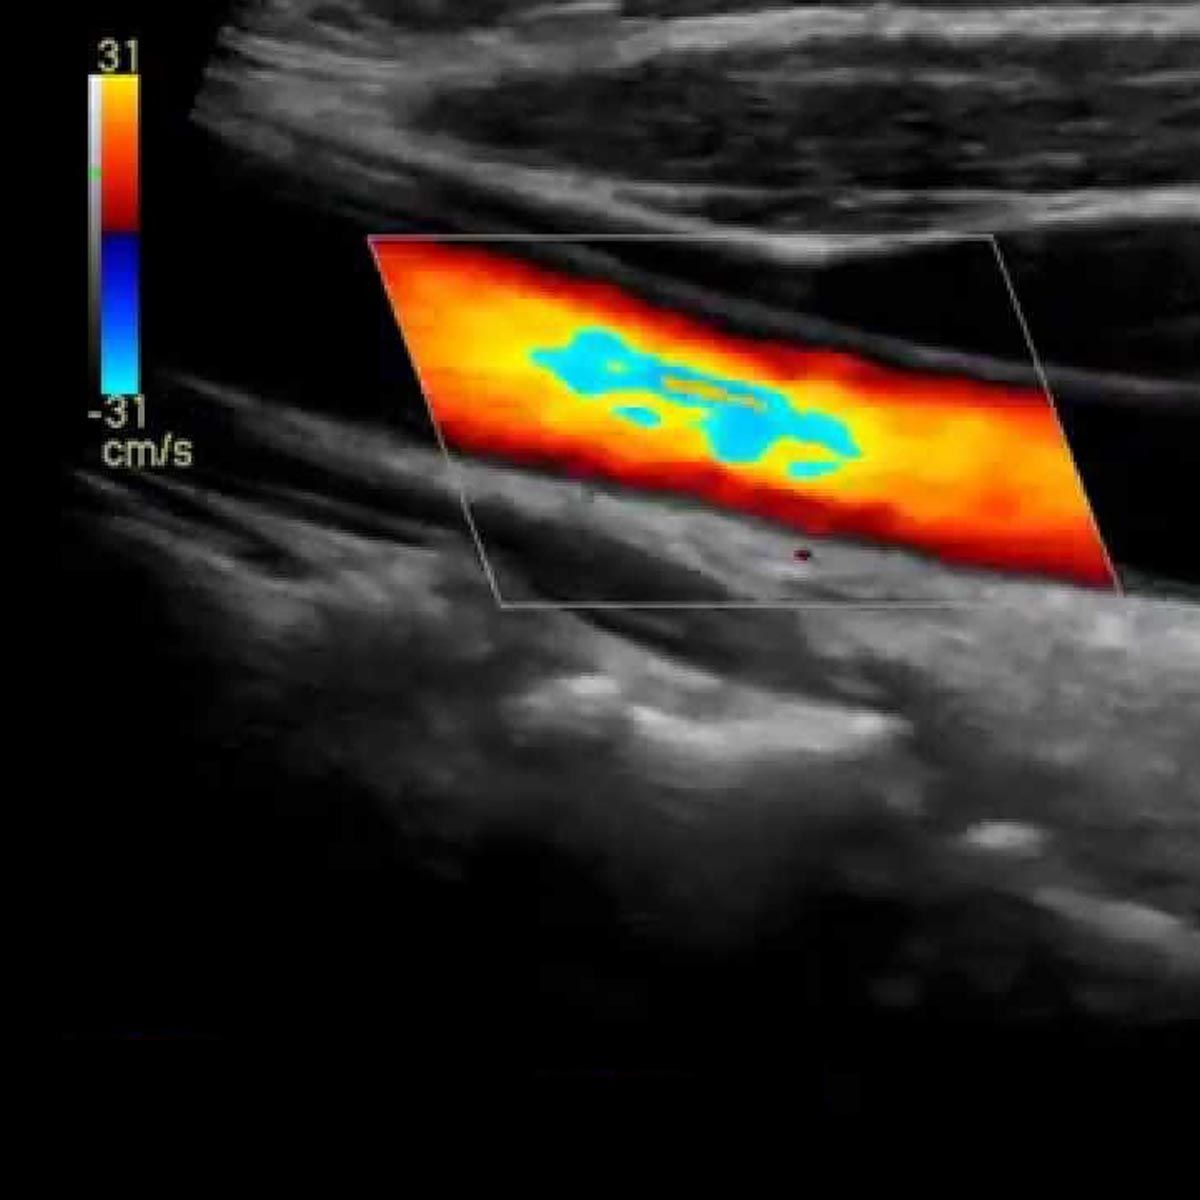

Durch die Anwendung von Doppler und Duplexultraschallverfahren und der Echokardiographie sind auch komplexe Fragestellungen im Bereich der Blutgefäße und des Herzens beantwortbar.